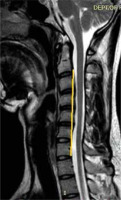

Figure 1

Sagittal T2W MRI image in a 23-year-old Hirayama disease patient showing kyphosis of the cervical spine. Posterior margins of the C3-C6 vertebrae are crossing the line drawn from inferodorsal aspect of C2 to inferodorsal aspect of C7 vertebral body

Normal cervical lordosis was lost in 10 (58.8%) patients with HD, which included straightening in 7 patients (41.1%) and kyphosis in 3 patients (17.6%) (Figure 1).

Loss of cervical lordosis has also been reported in the literature in patients with HD. In our study, loss of cervical lordosis was seen in 58.8% of patients in the form of straightening (41.1%) or kyphosis (17.6%), unlike Hassan et al., who found loss of cervical lordosis in 91% of patients in their study [29]. In spite of this, loss of lordosis, in particular cervical straightening, is a very non-specific finding that can be seen in a lot of patients.